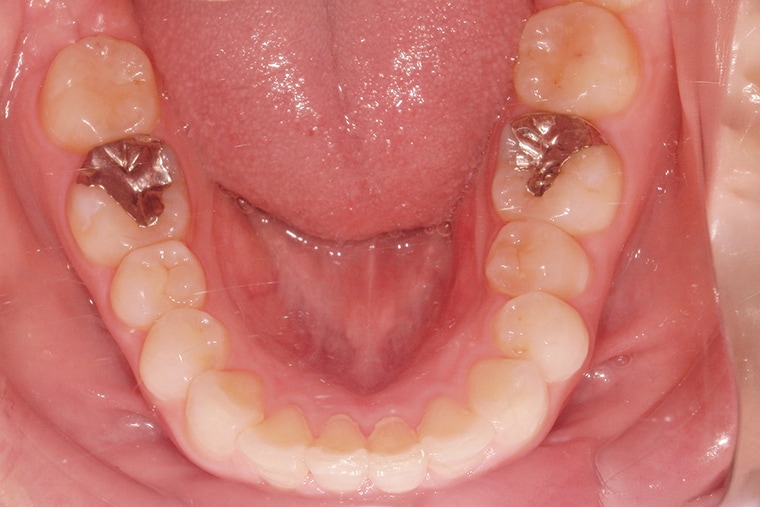

AFTER

約6ヶ月の治療を経て、下の歯のガタガタはきれいに整い、歯並びが改善されました。鏡で歯並びを見るたびに、自分の笑顔に自信が持てるようになり、以前のように口元を気にすることもなくなりました。

思っていた以上に短期間で変化を実感でき、痛みも最小限で済んだことがとても嬉しく、キレイになって満足です!